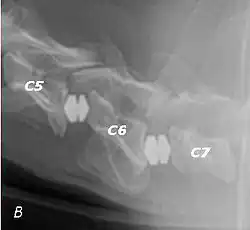

Wobbler disease is probably inherited in the Borzoi, Great Dane, Doberman, and Basset Hound.[2] Instability of the vertebrae of the neck (usually the caudal neck) causes spinal cord compression. In younger dogs such as Great Danes less than two years of age, wobbler disease is caused by stenosis (narrowing) of the vertebral canal[3] related to degeneration of the dorsal articular facets and subsequent thickening of the associated joint capsules and ligaments.[1] A high-protein diet may contribute to its development.[4] In middle-aged and older dogs such as Dobermans, intervertebral disc disease leads to bulging of the disc or herniation of the disc contents, and the spinal cord is compressed.[3] In Great Danes, the C4 to C6 vertebrae are most commonly affected; in Dobermans, the C5 to C7 vertebrae are affected.[5]

The disease tends to be gradually progressive. Symptoms such as weakness, ataxia, and dragging of the toes start in the rear legs. Dogs often have a crouching stance with a downward flexed neck. The disease progresses to the front legs, but the symptoms are less severe. Neck pain is sometimes seen. Symptoms are usually gradual in onset, but may progress rapidly following trauma.[6] X-rays may show misaligned vertebrae and narrow disk spaces, but it is not as effective as a myelogram, which reveals stenosis of the vertebral canal. Magnetic resonance imaging has been shown to be more effective at showing the location, nature, and severity of spinal cord compression than a myelogram.[7] Treatment is either medical to control the symptoms, usually with corticosteroids and cage rest, or surgical to correct the spinal cord compression. The prognosis is guarded in either case. Surgery may fully correct the problem, but it is technically difficult and relapses may occur. Types of surgery include ventral decompression of the spinal cord (ventral slot technique), dorsal decompression, and vertebral stabilization.[8] One study showed no significant advantage to any of the common spinal cord decompression procedures.[9] Another study showed that electroacupuncture may be a successful treatment for Wobbler disease.[10] A new surgical treatment using a proprietary medical device has been developed for dogs with disc-associated wobbler disease. It implants an artificial disc (cervical arthroplasty) in place of the affected disc space.[11]